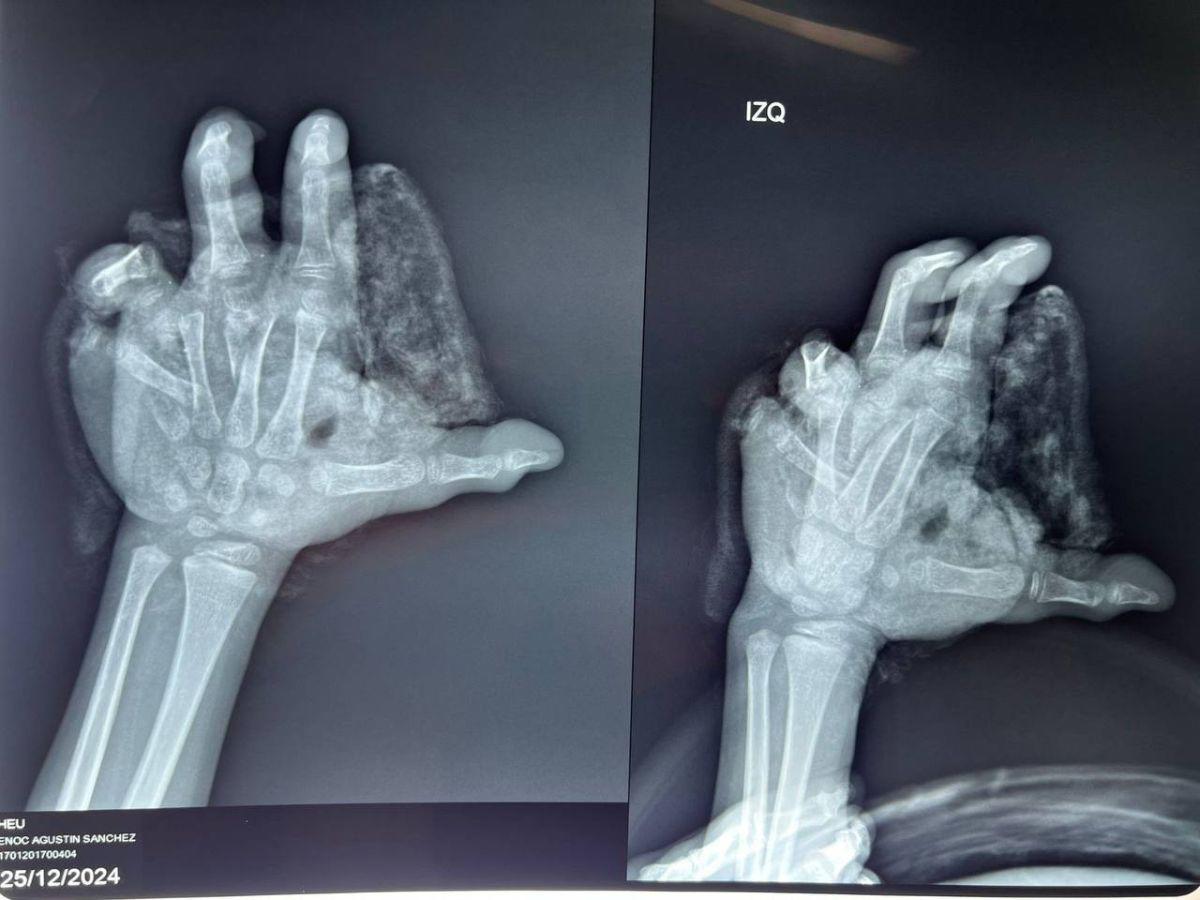

El pequeño sufrió graves lesiones en su mano izquierda. Las fotografías, que debieron ser censuradas por este rotativo, muestran el impacto devastador de la manipulación de pólvora en su extremidad.

Su mano llegó con un color morado, completamente destrozada y sin los dedos meñique y anular. Los médicos tuvieron que intervenirlo de inmediato debido a la gravedad de las lesiones.

Fueron más de 20 puntos de sutura los que se necesitaron para reconstruir la palma de su mano, que quedó irreconocible.

Además de los dos dedos amputados, el menor presentó lesiones en el dedo medio, donde también perdió parte de su uña.

El diagnóstico médico confirmó una fractura expuesta de huesos, así como la amputación total de los dedos meñique y anular.